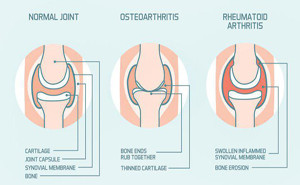

Osteoarthritis is a disease resulting

from wear and tear on joints over time, whereas Rheumatoid arthritis is an

autoimmune disease where the body’s immune system attacks joint tissues. RemoveAvailable Brand

The authors of this study

evaluated the association between weight loss and total knee or hip replacement

for osteoarthritis among middle-aged and older adults with overweight or

obesity. Compared with maintaining a stable weight, weight loss of >7.5% was

associated with a reduced risk of total knee but not total hip replacement.

A weight loss...